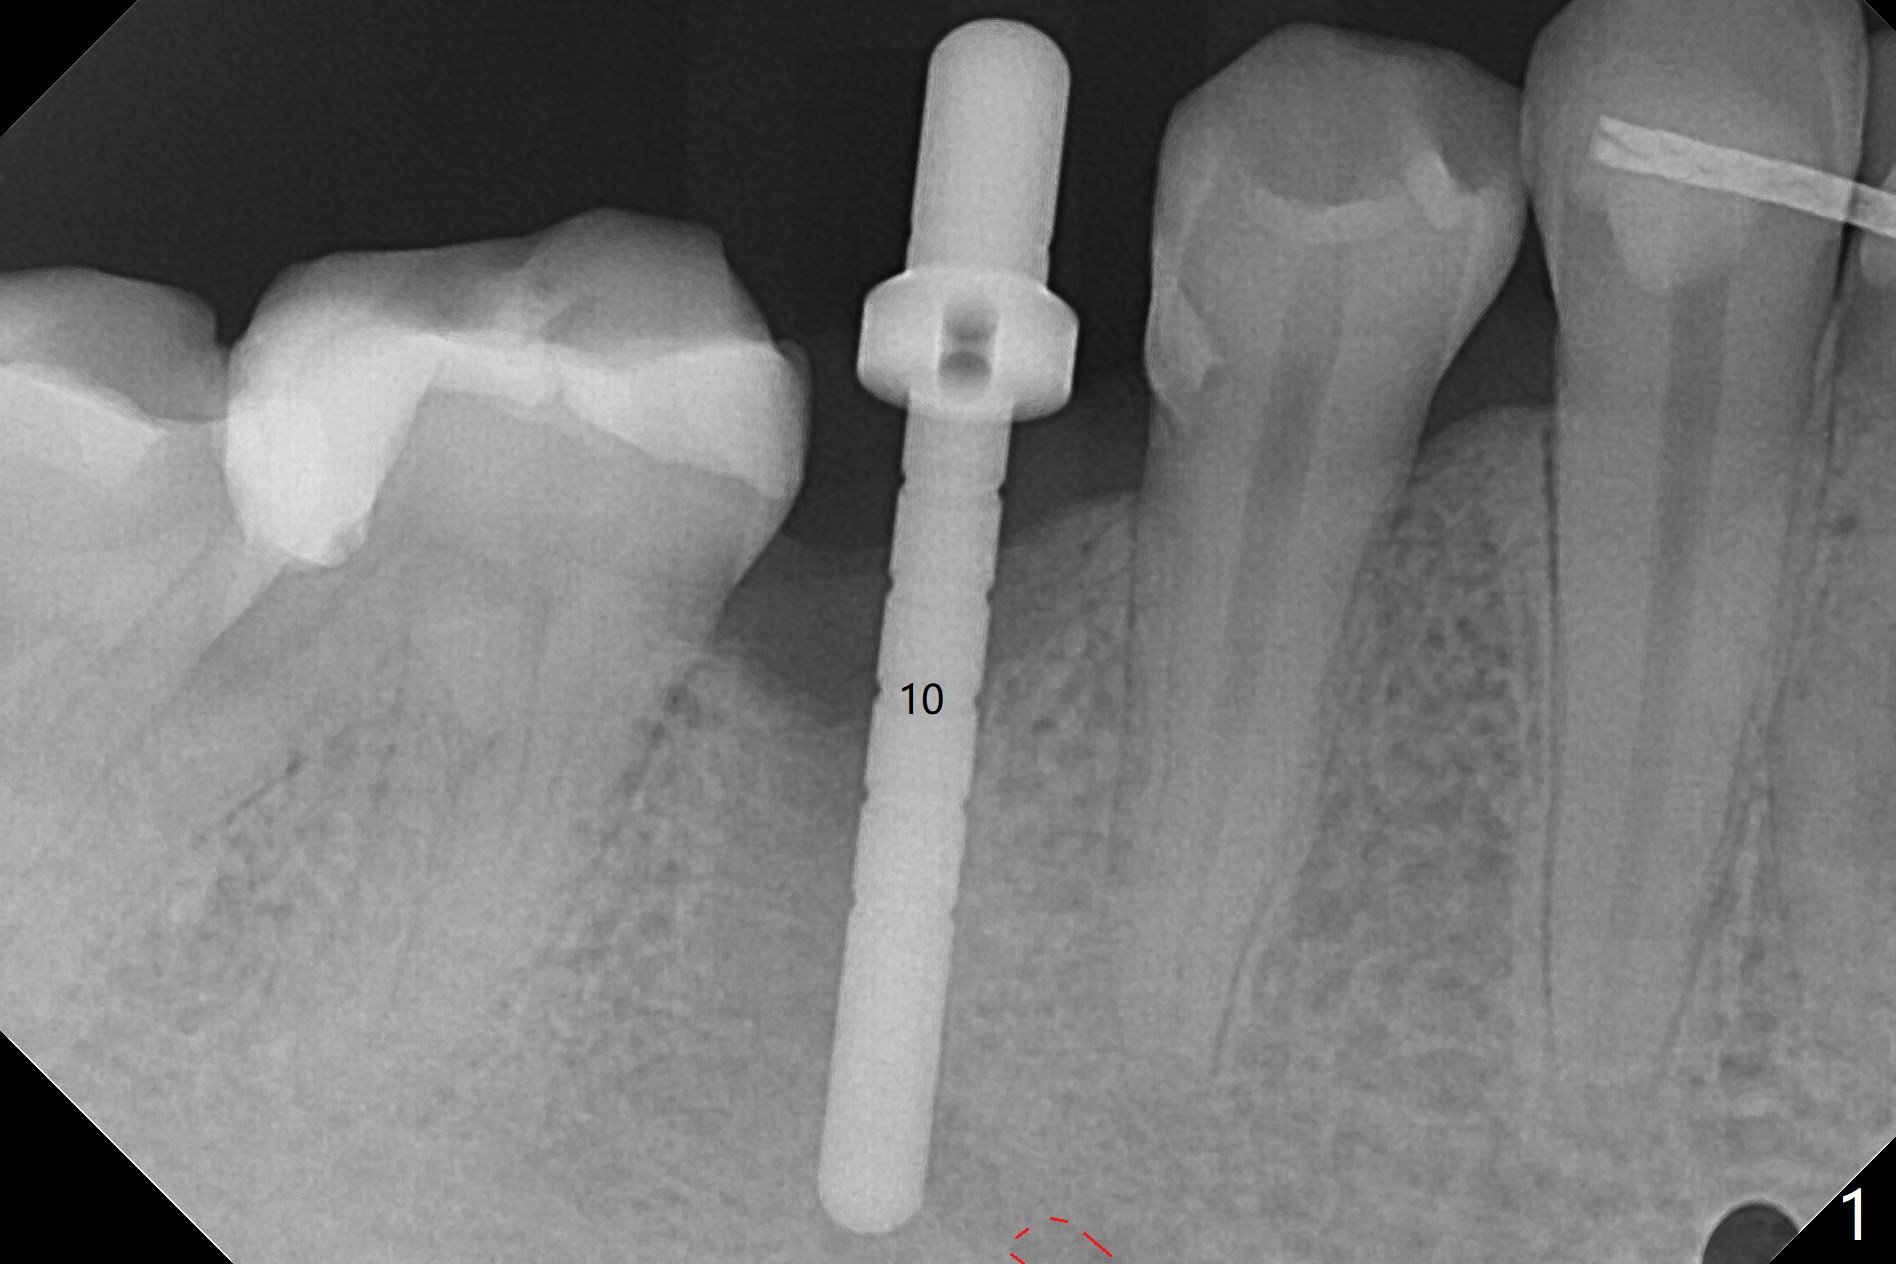

Osteotomy starts in the lingual slope of the socket of #29 with Point/Lindamann bur, but a little too distal. Gradually the osteotomy is moved mesial; the trajectory and position (Fig.1) are better than designed, but the osteotomy is close to the Mental Loop (red dashed line). When a 4x11.5 mm implant is placed, it appears to overlap the buccally positioned Loop (Fig.2 red dashed line). In fact there is no postop paresthesia. The implant placement level seems to be ideal (Fig.3 after bone graft). There is foul smell from the immediate provisional; in fact it may be due to the loose contact between the implant and abutment (Fig.4 < (4 months postop)). The gingiva is unhealthy. A 5.5x5 mm healing abutment is placed. When the patient returns 5 months postop, the gingiva is healthy after removal of the healing abutment. A 4.5x4(4) mm cemented abutment is seated without interference and torqued to 35 Ncm (Fig.5).